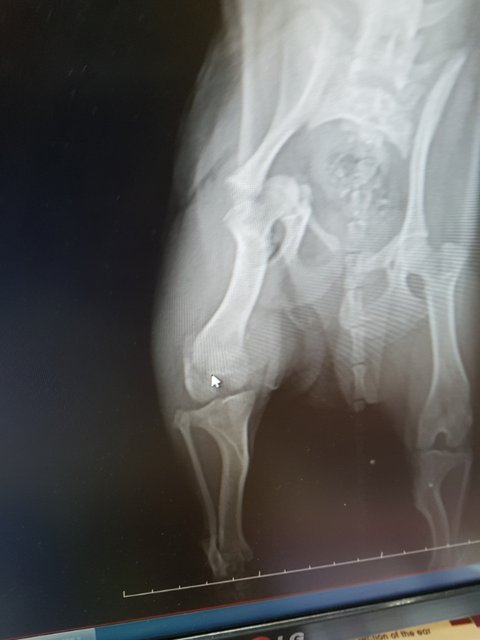

#김제보호소 #교통사고 #뒷다리골반복합골절 #사지말고입양하세요 #유기견입양 #살수있게도와주세요 #치료받을수있게도와주세요

검진을 다녀왔습니다

골반뼈..무릎뼈..복합골절..

다리부분에 피멍이 잔뜩 들어있습니다

수술비만 백만원이 넘는비용을 감당할 자신이 없습니다

여아 1~2살 3.9키로